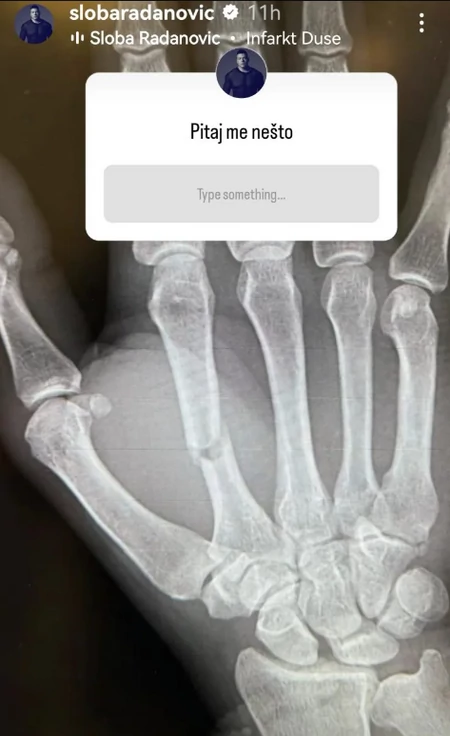

Još uvek nije poznato kako je pevač zadobio povredu ruke, ali je sada na svom Instagram profilu odlučio da podeli fotografije i obavesti fanove da će u ponedeljak morati da ide na operaciju.

Na fotografiji povređene ruke se vide šavovi i podlivi, pa se fanovi nadaju da će operacija proteći dobro i da će se Sloba brzo oporaviti.